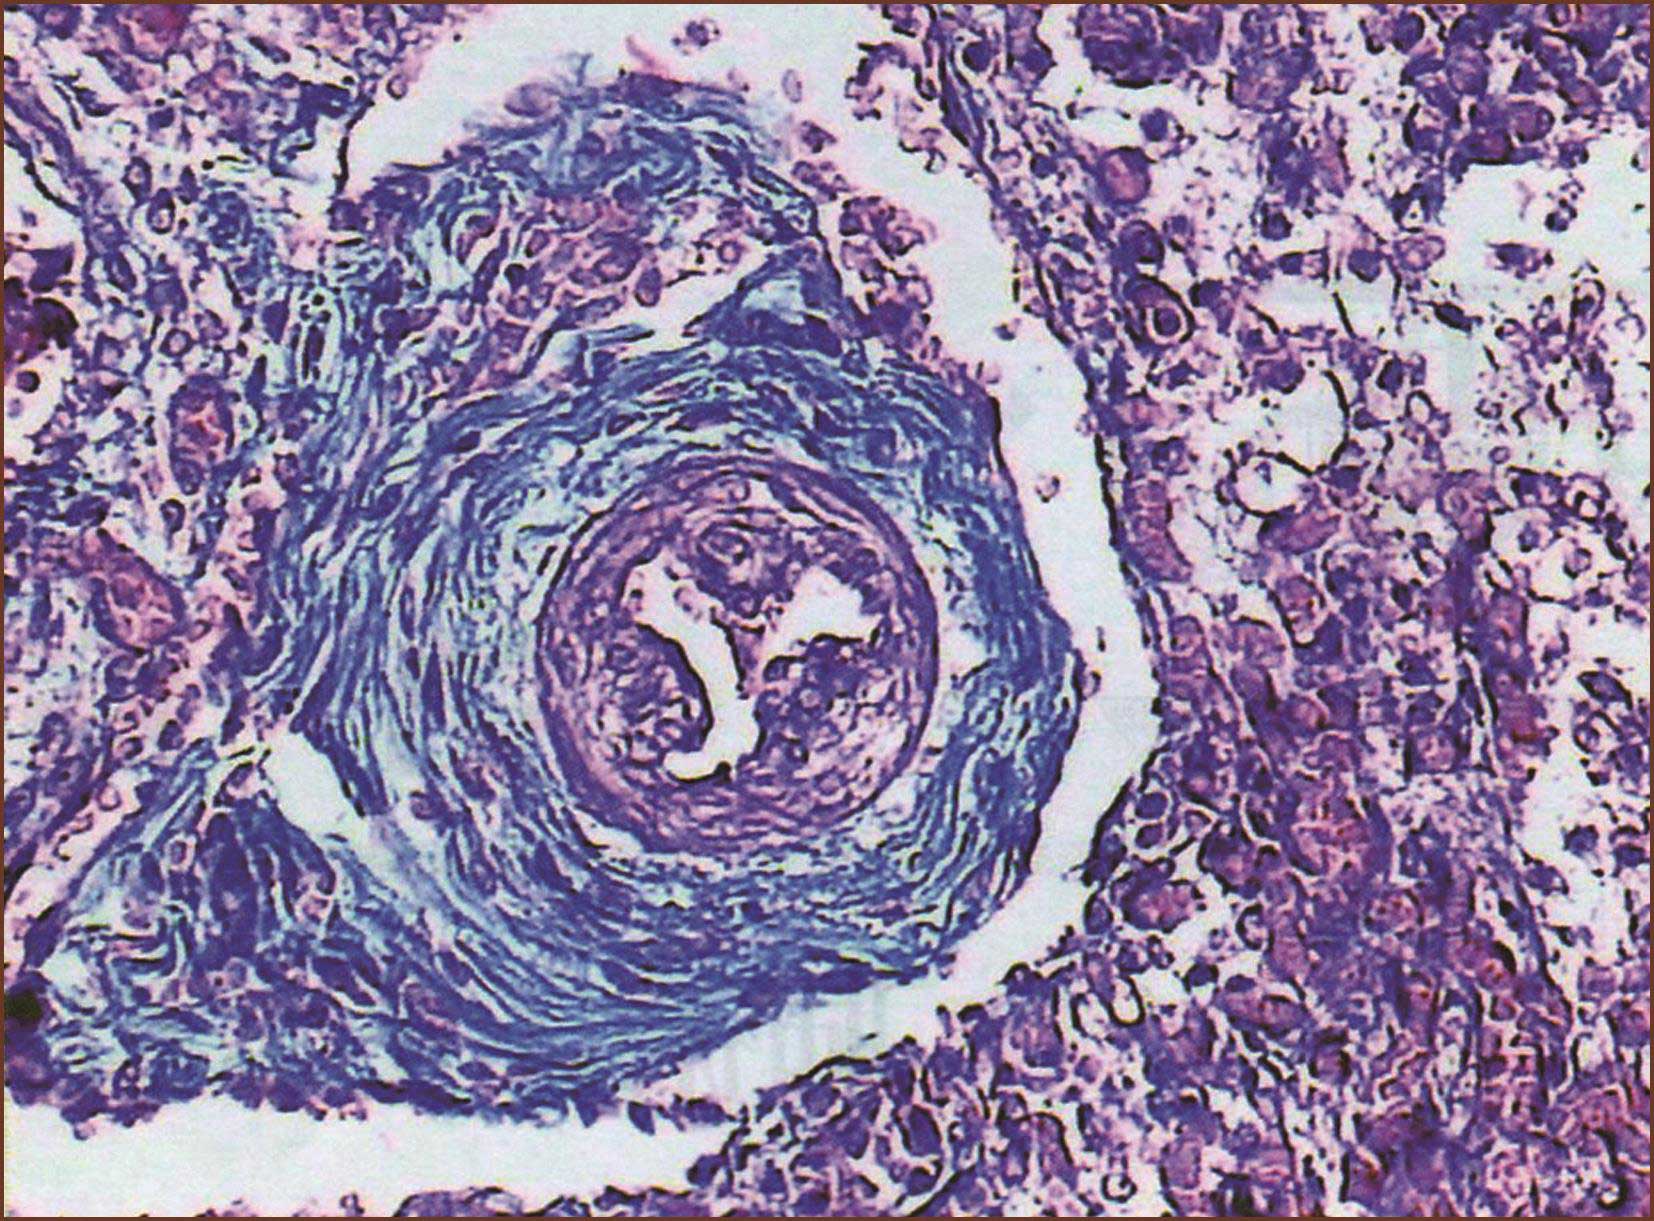

图1-3-11 正常胎儿肺内小动脉比正常成人肺小动脉中膜、外膜厚,内皮细胞胖大,呈乳头状突向管腔,肺泡腔未形成(Masson染色,中倍放大)